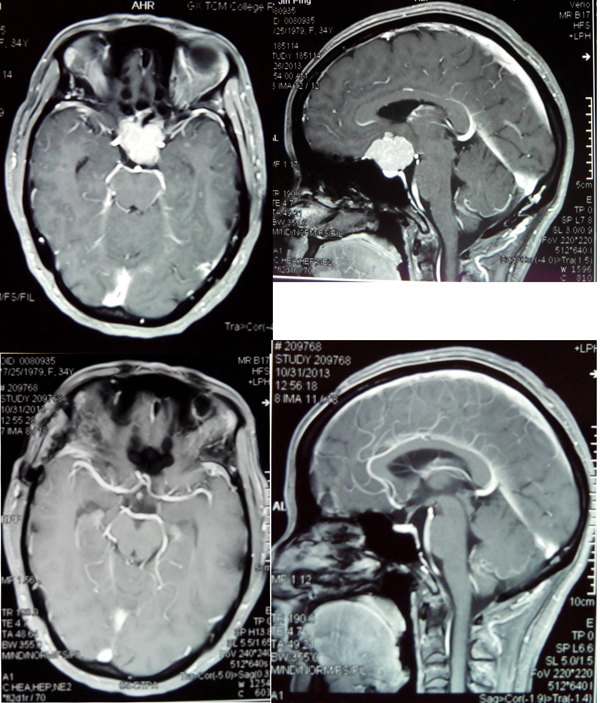

李老师进入我院时检查显示,左侧视力仅有1米指数,右侧视力仅有0.5米指数,佩戴眼镜后左侧视力0.1,右侧视力0.25。视力已接近失明,如果不及时治疗,最终将真正失明。

神经外科范学政主任和李亚平等医生认真分析了李老师的病情:肿瘤长在颅内鞍区,只能手术治疗,但是肿瘤与颈动脉和视神经的距离只有几毫米,手术稍有不慎就会损伤颈动脉引起大出血。如果损伤视神经则会失明,甚至有可能引起肿瘤周围的垂体等重要神经组织损伤,导致尿崩电解质混乱,昏迷甚至成为植物人。

带着李老师的重托,范主任认真制定了严密的手术方案,于7月31日主刀为其手术。范主任在显微镜下小心翼翼地操作,经过几个小时终于将肿瘤完全切除,而且没有损伤肿瘤周围的血管和神经,未出现任何并发症。术后2个月,李老师的视力已经明显恢复,再一次回到心爱的工作岗位。

上图为治疗前肿瘤,下图为治疗后肿瘤消失